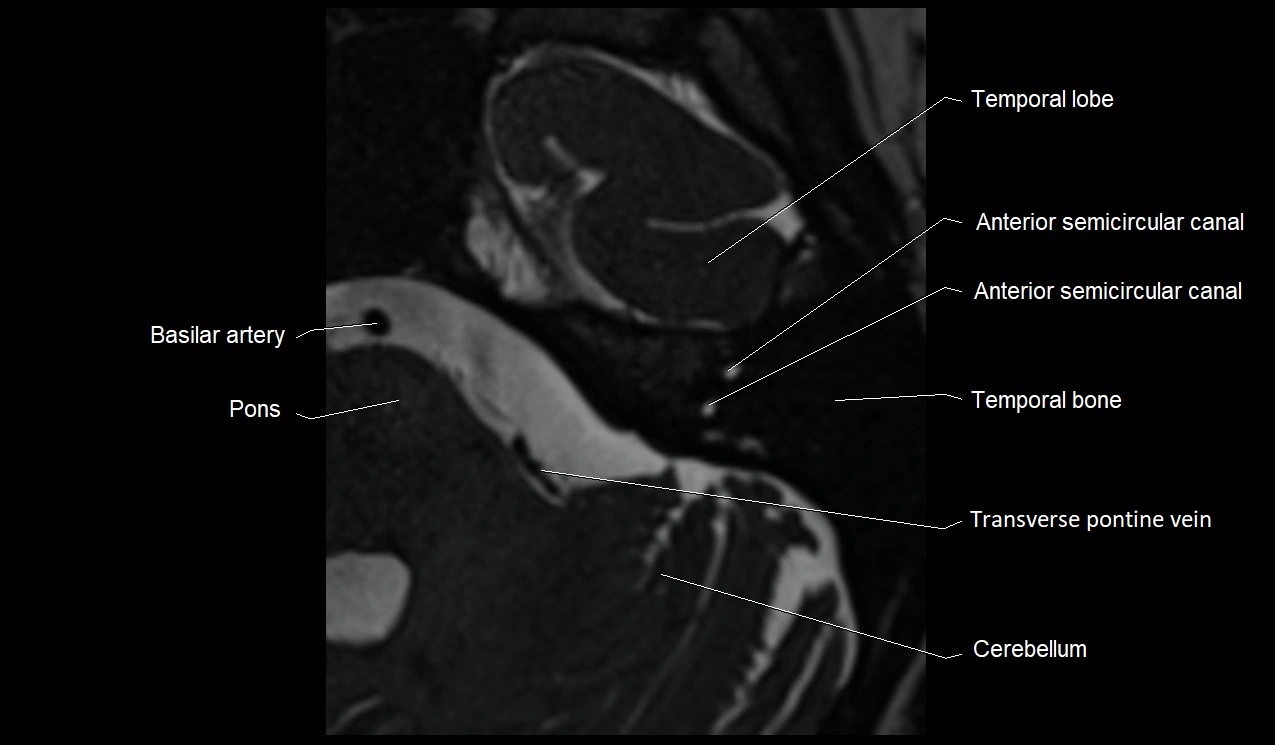

image